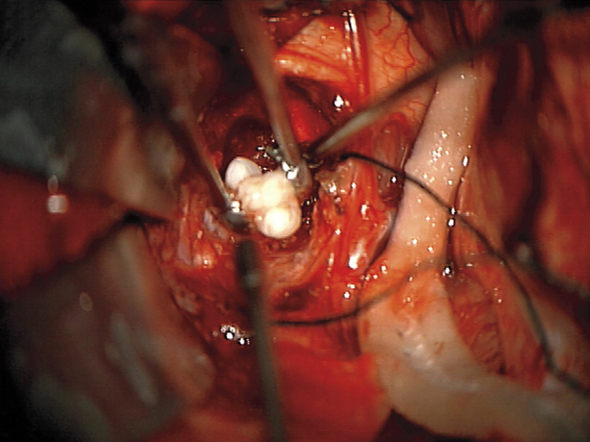

Dr. Narlin Beaty, neurocirujano en la Universidad de Maryland Medical Center, quien realizó la cirugía del niño, señaló que No todos los días se ven los dientes en cualquier tipo de tumor en el cerebro. En un craneofaringioma, es inaudito.

En el estudio, publicado, los investigadores sostienen que el tumor Craneofaringioma Adamantinomatosa (extirpado quirúrgicamente), surgió de la Bolsa de Rathke, precursor embrionario de una parte de la hipófisis. Esos tumores a veces están rellenos de líquido viscoso de color amarillo que contiene cristales de colesterol. Sin embargo, nunca antes se habían documentado casos con dientes dentro de ellos louis vuitton outlet